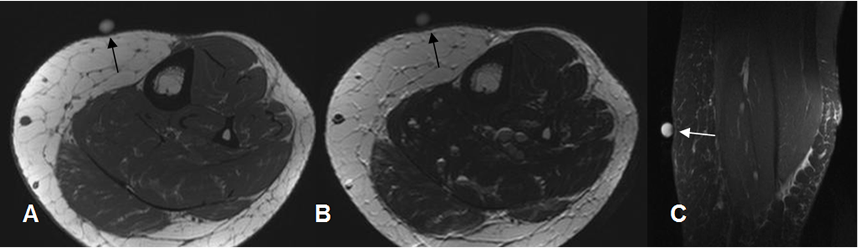

Fig 166 A. Lipomatosis.

A: RM axial en T, B: RM axial en T2 y C: RM sagital en STIR. Incremento difuso de la grasa, no encapsulado y localizado con marcador, que corresponde lipomatosis.